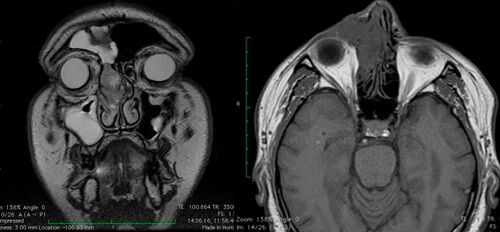

В диагностике инвертированных папиллом ключевое место занимают лучевые методы исследований

- компьютерная томографии

- магнитно-резонансная томографии (с контрастом по назначению врача).

Ценность КТ – материалов состоит в возможности точной оценки границ опухоли, что позволяет определить стадию процесса и тактику дальнейшего ведения больного. МР-данные позволяют дифференцировать активный воспалительный процесс в пазухах от фиброзной и рубцово-измененной ткани. Введение контрастного препарата повышает яркость свечения воспаленной слизистой оболочки.